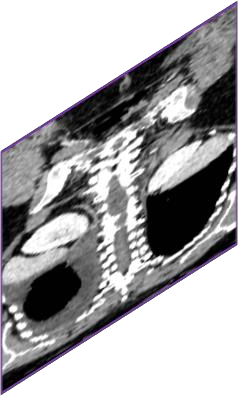

Due to the constraints of the imaging device and high cost in operation time, computer tomography (CT) scans are usually acquired with low intra-slice resolution. Improving the intra-slice resolution is beneficial to the disease diagnosis for both human experts and computer-aided systems. To this end, this paper builds a novel medical slice synthesis to increase the between-slice resolution. Considering that the ground-truth intermediate medical slices are always absent in clinical practice, we introduce the incremental cross-view mutual distillation strategy to accomplish this task in the self-supervised learning manner. Specifically, we model this problem from three different views: slice-wise interpolation from axial view and pixel-wise interpolation from coronal and sagittal views. Under this circumstance, the models learned from different views can distill valuable knowledge to guide the learning processes of each other. We can repeat this process to make the models synthesize intermediate slice data with increasing inter-slice resolution. To demonstrate the effectiveness of the proposed approach, we conduct comprehensive experiments on a large-scale CT dataset. Quantitative and qualitative comparison results show that our method outperforms state-of-the-art algorithms by clear margins.